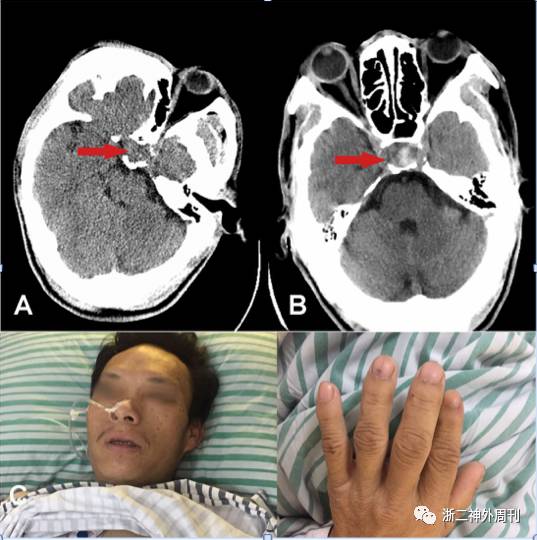

手术所见:在完善相关检查,排除手术禁忌,补足激素和纠正高血糖后,患者在全麻下接受经鼻蝶鞍区肿瘤切除术。术中打开鞍底硬膜后,可见肿瘤中大量陈旧性血性混合豆腐渣样组织(图5B),肿瘤质地软,血供一般,刮匙予以各个方向充分刮除后,可见塌陷的鞍底,肿瘤近全切除,然后用人工脑膜以及带蒂黏膜瓣进行颅底重建,手术过程顺利。

图5. 术中所见:A. 切开鞍底硬膜后可见陈旧性暗红色血性组织流出;B. 肿瘤深部可见豆腐渣样出血坏死组织,质韧。